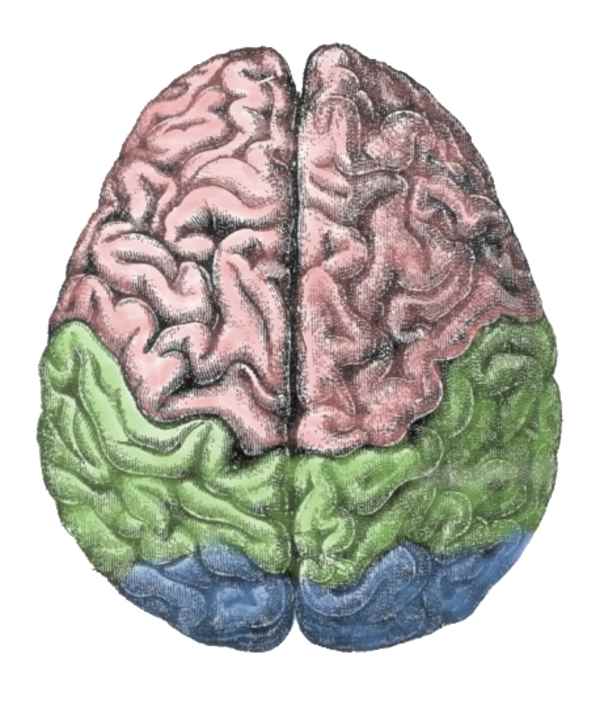

1872年10月17日

C.E. Brown-Sequard提出了革命性的脑功能理论,认为一侧大脑半球可以影响两侧的躯体。